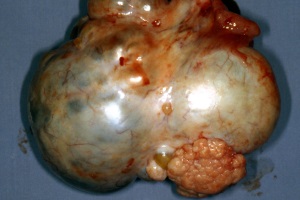

Ежегодно в мире регистрируют около 170 000 новых случаев рака яичников и около 100 000 женщин гибнут от прогрессирования заболевания.